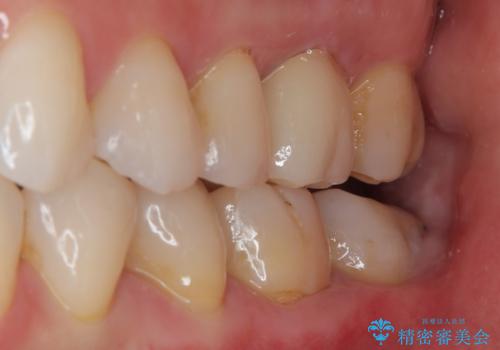

特に異常もなく見た目、噛み合わせともに満足していただけました。

ラバーダム防湿を行い、セラミックの接着をすることで、唾液や血液などの接着阻害因子を排除することができます。

歯と歯の間の虫歯をコンポジットレジンや保険のメタルインレーで治すと段差ができたりして清掃性が悪くなるので、セラミックインレー修復やゴールドインレー修復などの適合の良い詰め物で治療することをオススメします。